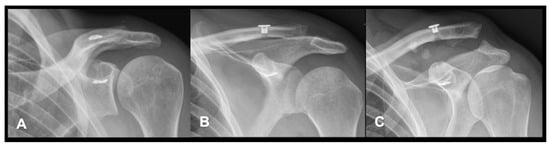

2.4. Radiographic Evaluation

3.3. Radiographic Evaluation

3.4. Intervention-Specific Outcomes